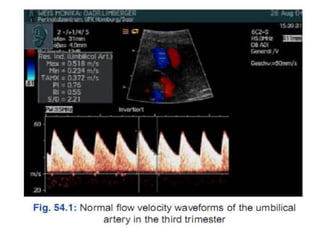

• DOPPLER OF THE UMBILICAL ARTERY

• Reduced end diastolic flow.

• Absent end diastolic flow

• Reversed end diastolic flow( severe cases)